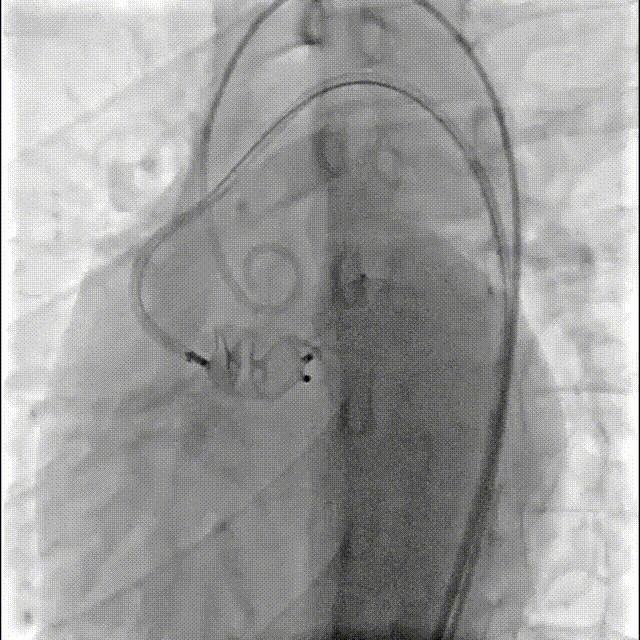

释放16mmAVP-II血管封堵器

术后造影提示封堵器位置良好